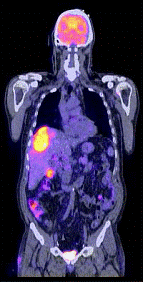

Fig. 8- Metastaze intrahepatice: imagini PET (18FFDG), CT si PET-CT.

sectiuni transversale (stanga) si sectiuni coronale (dreapta)

Indicatiile clinice ale PET-CT sunt, de fapt, identice cu acelea ale PET, referindu-se indeosebi la domeniul oncologiei nucleare: diagnostic tumoral (Fig. 6, 8,) stadializare (Fig.9) si evaluare evolutiva (Fig. 10), pre- si post- terapie . Evident, metoda PET-CT prezinta o serie de avantaje fata de fiecare dintre cele doua metode utilizate separat: